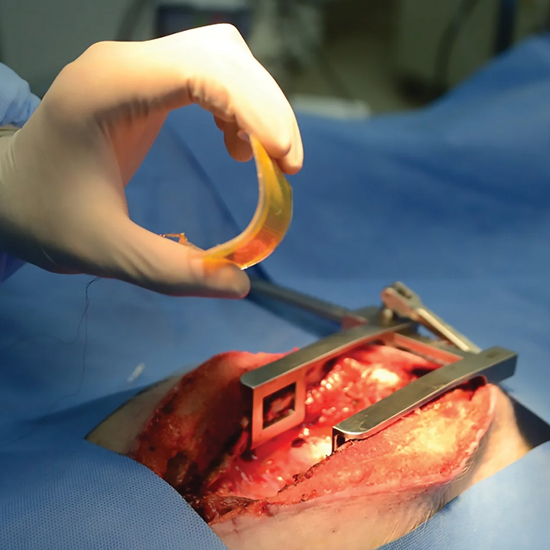

Angiography is an imaging test that uses X- rays to view your body's blood vessels.

Angioplasty also known as balloon angioplasty abd percutaneous transluminal angioplasty